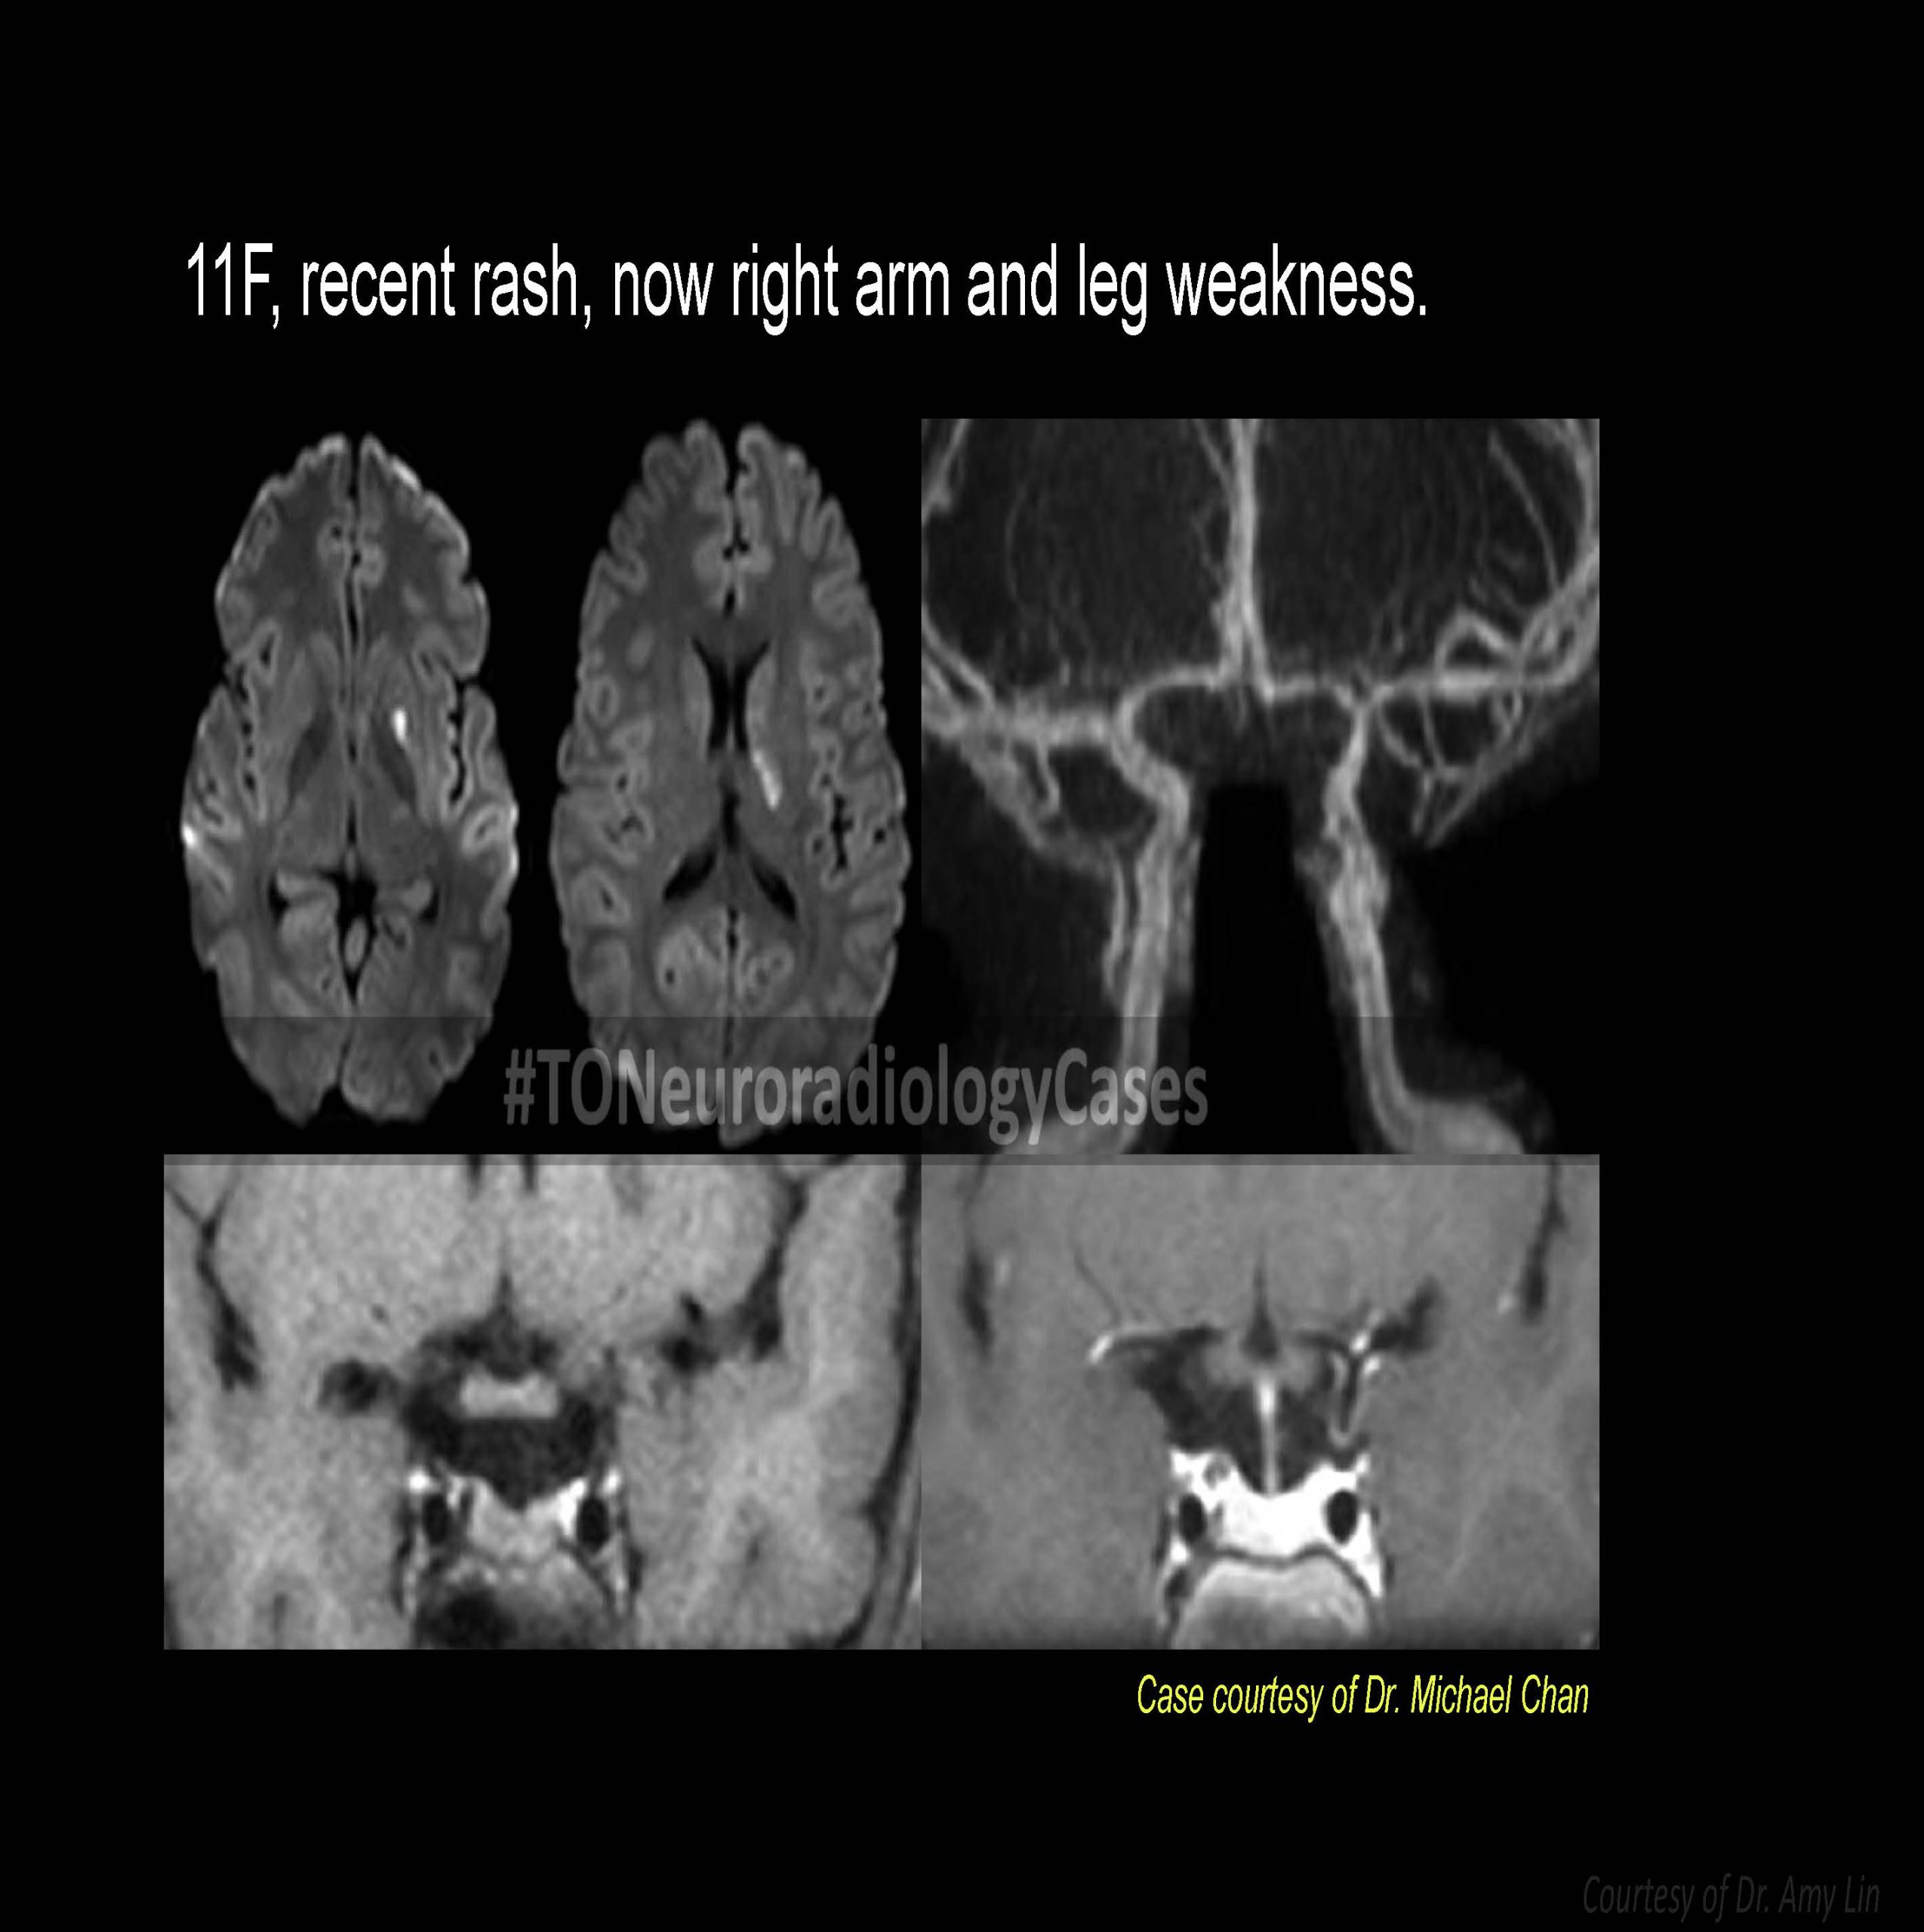

DR. AMY CHEN’S

Neuroradiology Case of the Week

@ Toronto Radiology

Over the past few years, I’ve had the pleasure of curating a “Case of the Week” contest with contributions from radiologists across the city, designed to challenge and engage our neuroradiology fellows at the University of Toronto. This collection showcases a range of neuroradiology cases from our city and have been a fun part of our fellow’s educational experience. I am excited to share this resource with a wider audience, now featured on our Toronto Radiology departmental website.